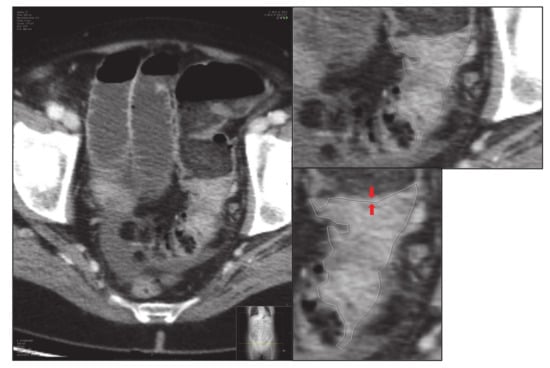

- Secondly, an expert radiologist delimits the tumour, and an image of the delimited tumour is saved in its original size: “large-delimited.tiff” (i.e., Figure 2). The delimitation process is carried out manually by an expert, since due to the morphological heterogeneity of the tumour it is impossible to make an automatic delimitation.